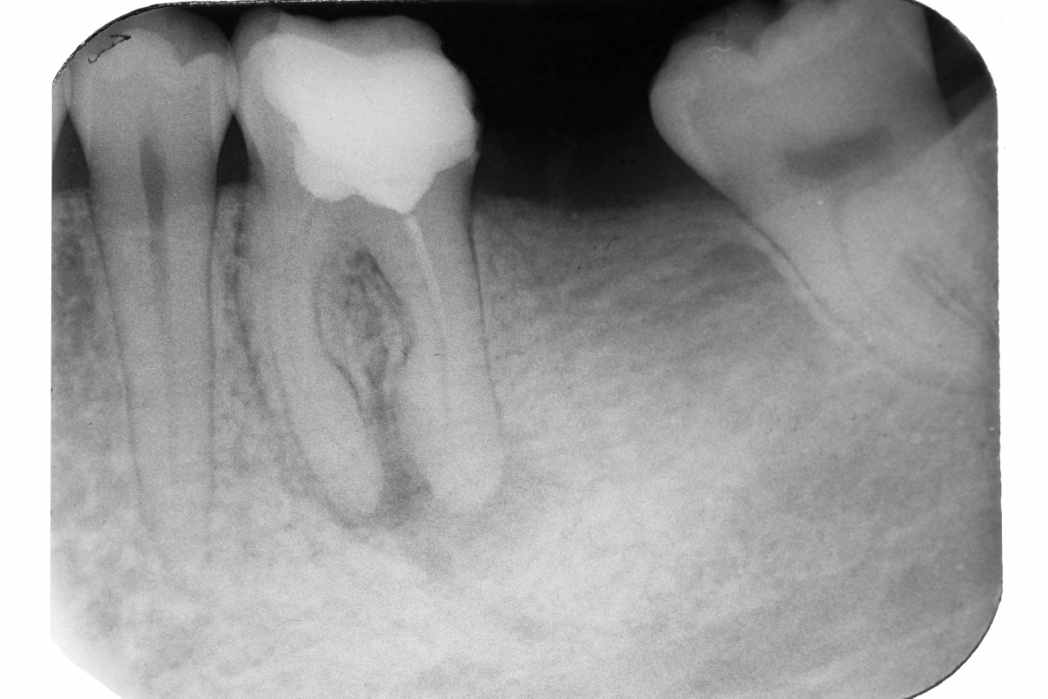

Пациент 35 лет обратился в клинику с жалобами на боль, усиливающуюся при накусывании. В ходе обследования поставлен диагноз обострение хронического гранулирующего периодонтита. На рентгенограмме (рис 1а) нижний первый моляр с неадекватно запломбированными корневыми каналами, в периапикальной области обширный очаг разрежения костной ткани. Лечение: удаление пломбы, создание доступа к устьям корневых каналов, распломбирование дистального канала, проведение инструментальной и медикаментозной обработки корневых каналов. После инструментальной обработки проводим ирригацию корневых каналов эндодонтическим шприцом с эндо иглой и 0,5 % раствора гипохлорита натрия для качественной медикаментозной обработки корневых каналов. Лечение зуба проводили с применением временной антибактериальной повязки на основе гидроксида кальция, который вводили в корневые каналы в виде жидкой суспензии. Временную повязку меняли каждые 2 недели, поскольку она начинала растворяться. Через 3 месяца временную повязку удаляли, канал пломбировали силером с гуттаперчей.

Рис 1а. Рентгенологический снимок до лечения

Рис.1б. Рентгенологический снимок после лечения

На контрольной рентгенограмме (рис 1 б) каналы обтурированы герметично на всем протяжении до верхушек, отмечается незначительное выведение пломбировочного материала за верхушку дистального корня. Пациенту рекомендовано явиться на контрольный рентгенологический снимок через 6 месяцев.